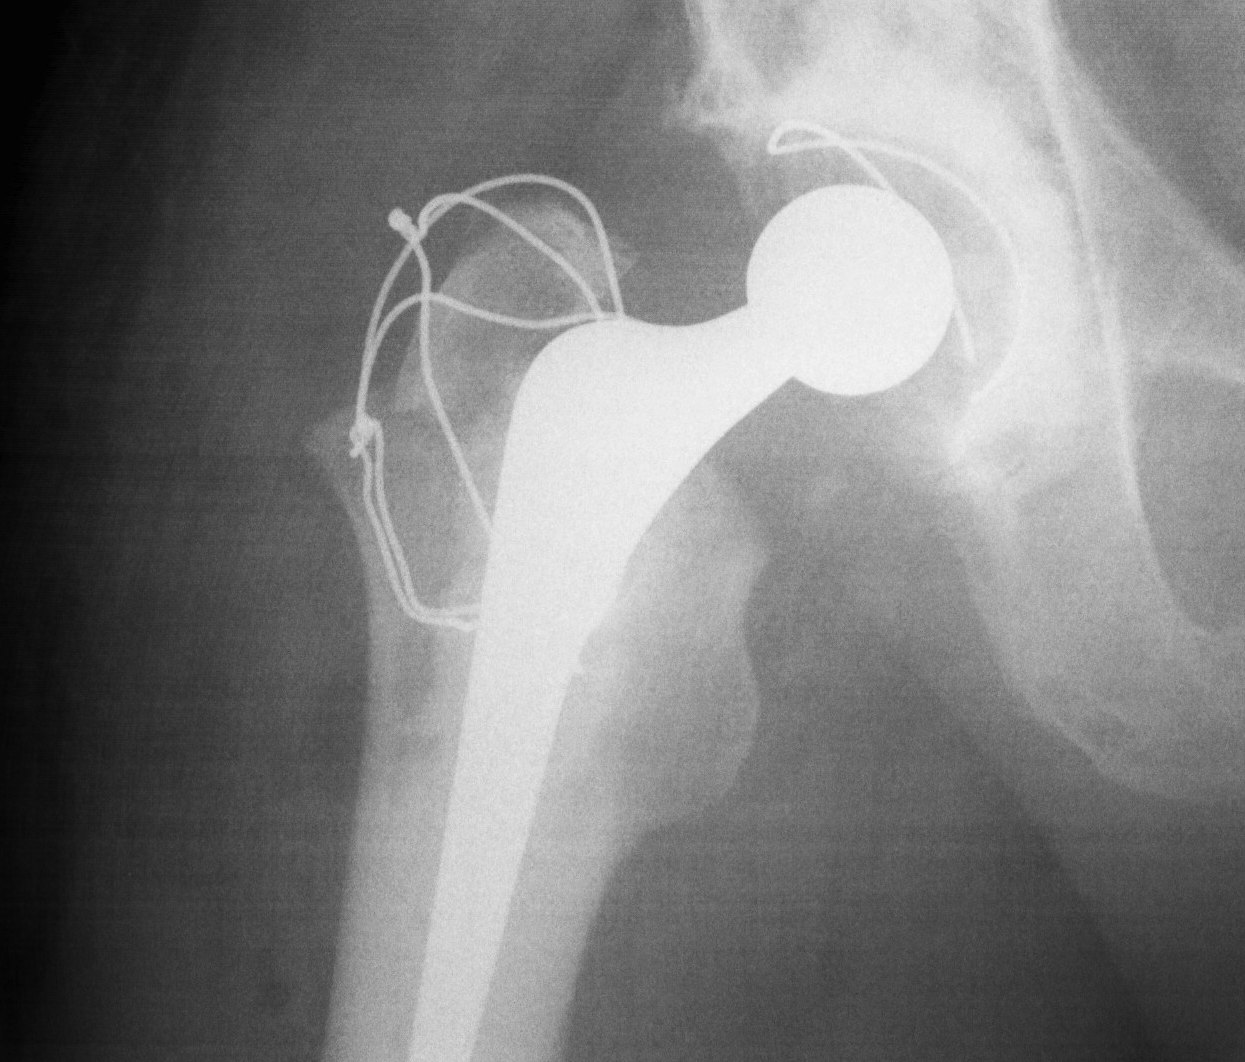

Trochanteric Slide

Concept

- PA osteotomy

- vastus lateralis and G medius left attached to fragment

- fragment retracted anteriorly

Advantage

- increased inherent stability

- vastus lateralis prevents proximal migration

Technique

- retractor superiorly deep to minimus and superior to capsule

- posterior elevation of vastus lateralis

- retractor under vastus lateralis insertion

- oscillating saw anterior to posterior

Fixation

- wires

- grip plate